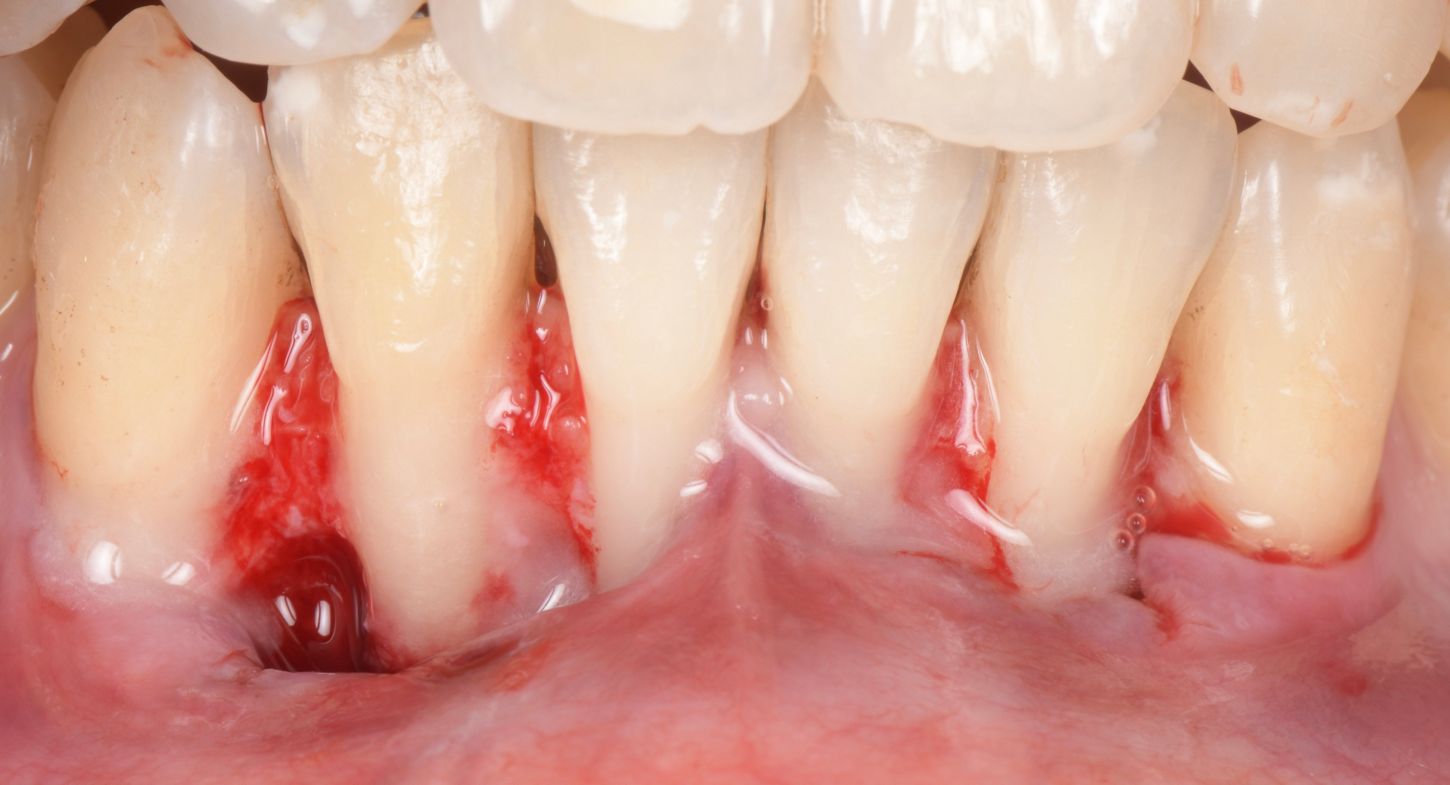

A 35-year-old female, healthy (ASA I), non-smoker, with no medication, came to our practice complaining about gingival recession and pain while brushing her mandibular incisors.

The intraoral examination revealed multiple RT 1 (Cairo 2011) gingival recessions on teeth #33 to #43, along with a thin tissue phenotype, which was associated with a traumatic toothbrushing habit (Fig. 1).

Two split-full-split flaps were raised from teeth #33 to #31 and #41 to #43, with beveled incisions at the base of the papilla (Fig. 3).

De-epithelialization of the anatomical papilla (Fig. 4).